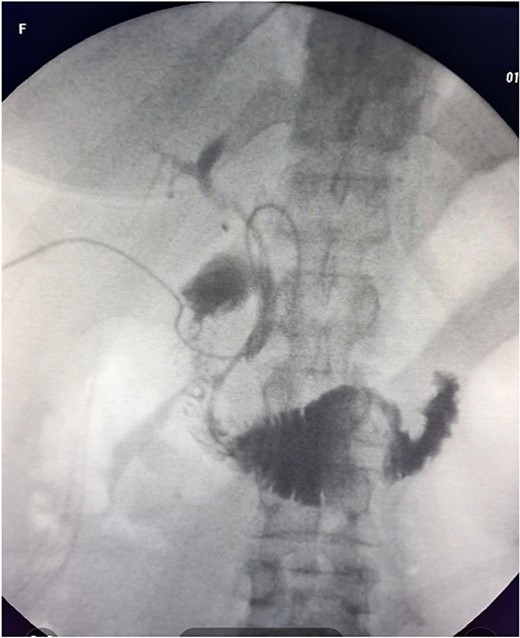

The patient was scheduled for a laparoscopic cholecystectomy the following day. Intraoperatively, an enlarged gallbladder hydrops with the presence of various caliber calculi in the lumen, the largest of which measured 2 cm/d, was found. The contents of the bladder are punctured and evacuated to facilitate its grasping in the fundus area and creating a good exposure of Callot’s triangle. Using a four trocar technique, a dissection was performed in the triangle of Callot, noting the difficult manipulation in the area between cystic duct and common hepatic duct. The cystic duct is identified to its confluence with the common bile duct at a 45° angle. The cystic artery was also visualized, after which clips were placed on both structures after ensuring that they entered the gallbladder. Dissection of the gallbladder in its distal part, attached to the liver parenchyma above Rouvier’s line, was started using electrocautery and hook. The tissue density of a limited area in the distal part between the wall of the gallbladder and the liver parenchyma was dissected using a hook. A bile duct was opened in its unusual anatomical location (Fig. 1). Due to lack of equipment for intraoperative cholangiography, it was converted to open access and subsequent revision of the extrahepatic bile ducts. The common bile duct and right–left hepatic duct were mobilized to the site of entry into the liver parenchyma. A parietal lesion of the right hepatic duct just above the confluence and anatomical integrity of the common bile duct and left hepatic duct were found. After examining the removed gallbladder, it was found that it was immediately flowing into a duct which connects the cystic duct with the right hepatic duct as depicted in Fig. 2. A plasty of the right hepatic duct was performed, and prior to this duodenotomy and papillotomy were performed by mobilization of the duodenum according to Kocher. A protective drain was placed in the choledochus draining from the right hepatic duct to the ampulla of Vater. Separetely, the clips previously placed on the cystic duct were removed and a transcystic drain was placed; a leak test was performed at the plastic site of the right hepatic duct. The postoperative period was without complications. From the transcystic drain, the secretion of bile stopped on the fourth postoperative day. On the eighth postoperative day, transdrainage cholangiography was performed; the common bile duct and bought hepatic ducts were imaged, and free passage of the contrast material through the duodenum was established (Fig. 3). The transcystic draine was removed on the 20th day of surgery.

Visualization of the biliary lesion; (1) tangential damage to the right hepatic duct; (2) gallbladder with lateral traction.

Anatomical varieties include congenital anomalies of the bile ducts, and in 2013, Patil et al. [1] described a total of 12 cases of anomalies of cystic duct, of which 11 were congenital. They should be well known by the surgeon given the difficulties they can cause during cholecystectomy. The length and course of cystic duct and its connection pattern with common hepatic duct (CHD) are variable and it is not necessary to outline its entire course and its point of confluence with CHD during cholecystectomy according to Gupta et al. [4], as it would place the bile duct at risk of injury, especially in cases where the cystic duct adheres to CHD due to inflammation. The first difficulty in performing a dissection in the region of Calot’s triangle during cholecystectomy in the case described by us is precisely such an increase in the angle between cystic duct and CHD, as illustrated in Fig. 1. All the time on the cholecystectomy but actually a mobilization of the structures cephalade relating to the defensive line described by Gupta et al. [4] as R4U line (Rouviere’s sulcus-Segment 4-Umbilical fissure).